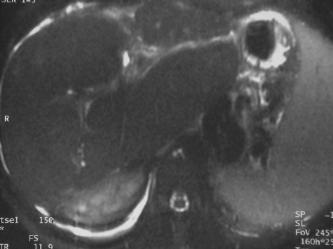

Patiente de 24 ans

opérée à l'âge de 1 ans d'une atrésie des voies biliaires (opération de Kasaï pour agénésie du cholédoque)

actuellement bilan pré greffe hépatique pour HTP sévère avec hémorragie digestive.

Hypertension portale sévère avec importante splénomégalie et varices oesophagiennes bien visible sur la séquence pondérée T1 après injection de gadolinium. Fibrose hépatique avec augmentation des structure hypo T1 et hyper T2 autour de la veine porte intra hépatique qui est de petit calibre mais perméable prédominance de la vascularisation artérielle est "trop" bien visible. Absence de dilatation des voies biliaires même à la périphérie du foie. Le lobe caudé est très hypertrophique ainsi que le segment IV, les autres segments sont atrophiques. Cet aspect est en faveur d'une slérose hépatoportale.

Bili IRM coupe épaisse pas de dilatation périphérique mais irrégularité des voies biliaires proximales.